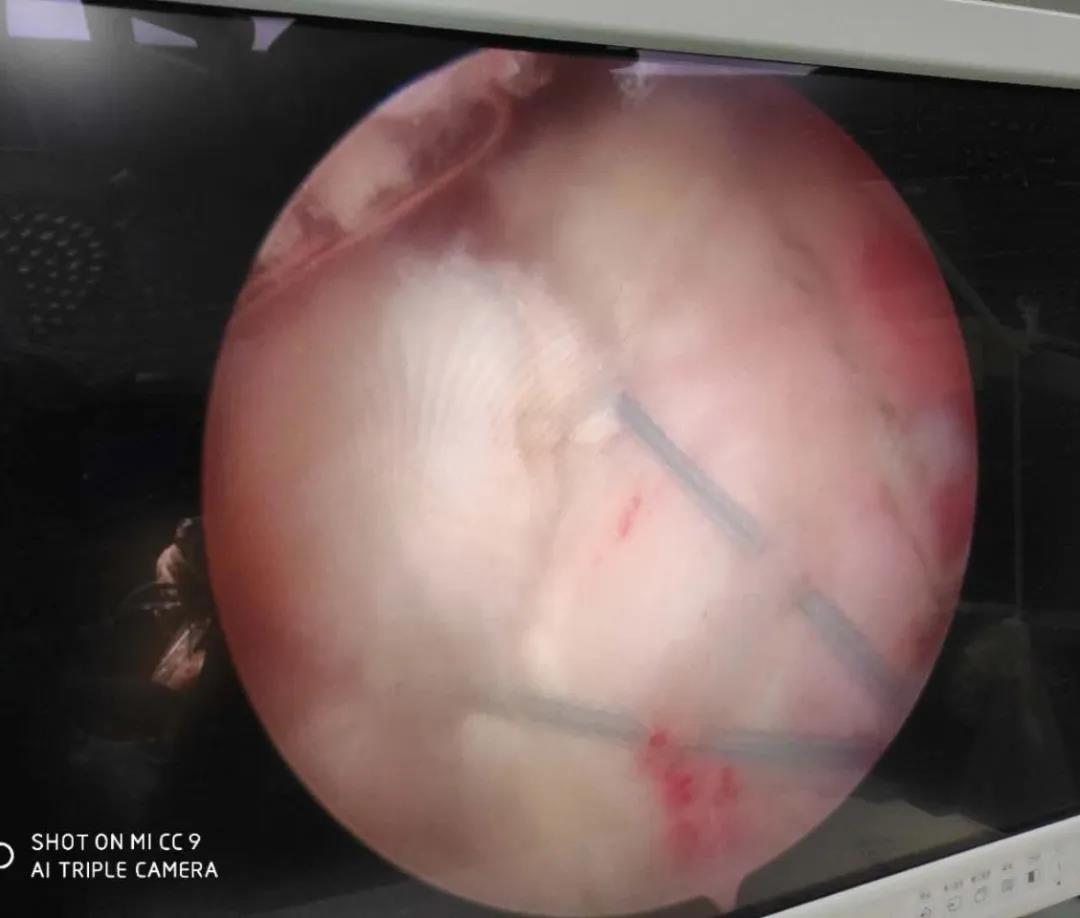

膝關(guān)節(jié)半月板損傷和前后交叉韌帶損傷是運(yùn)動損傷常見疾病,半月板損傷后不能自行愈合,盡早手術(shù)可以避免繼發(fā)關(guān)節(jié)軟骨的損傷,骨二科采用關(guān)節(jié)鏡下半月板縫合手術(shù),能少切除就少切除,能縫合盡量縫合,最大努力保留患者半月板,更好的恢復(fù)膝關(guān)節(jié)的功能。膝關(guān)節(jié)前后交叉韌帶損傷一般采用單束重建,只能恢復(fù)原來韌帶的80%的強(qiáng)度,骨二科采用雙束重建,能夠比原來的韌帶更粗更強(qiáng),為后期的功能鍛煉及恢復(fù)提供良好的基礎(chǔ)。

關(guān)節(jié)鏡下半月板縫合手術(shù)